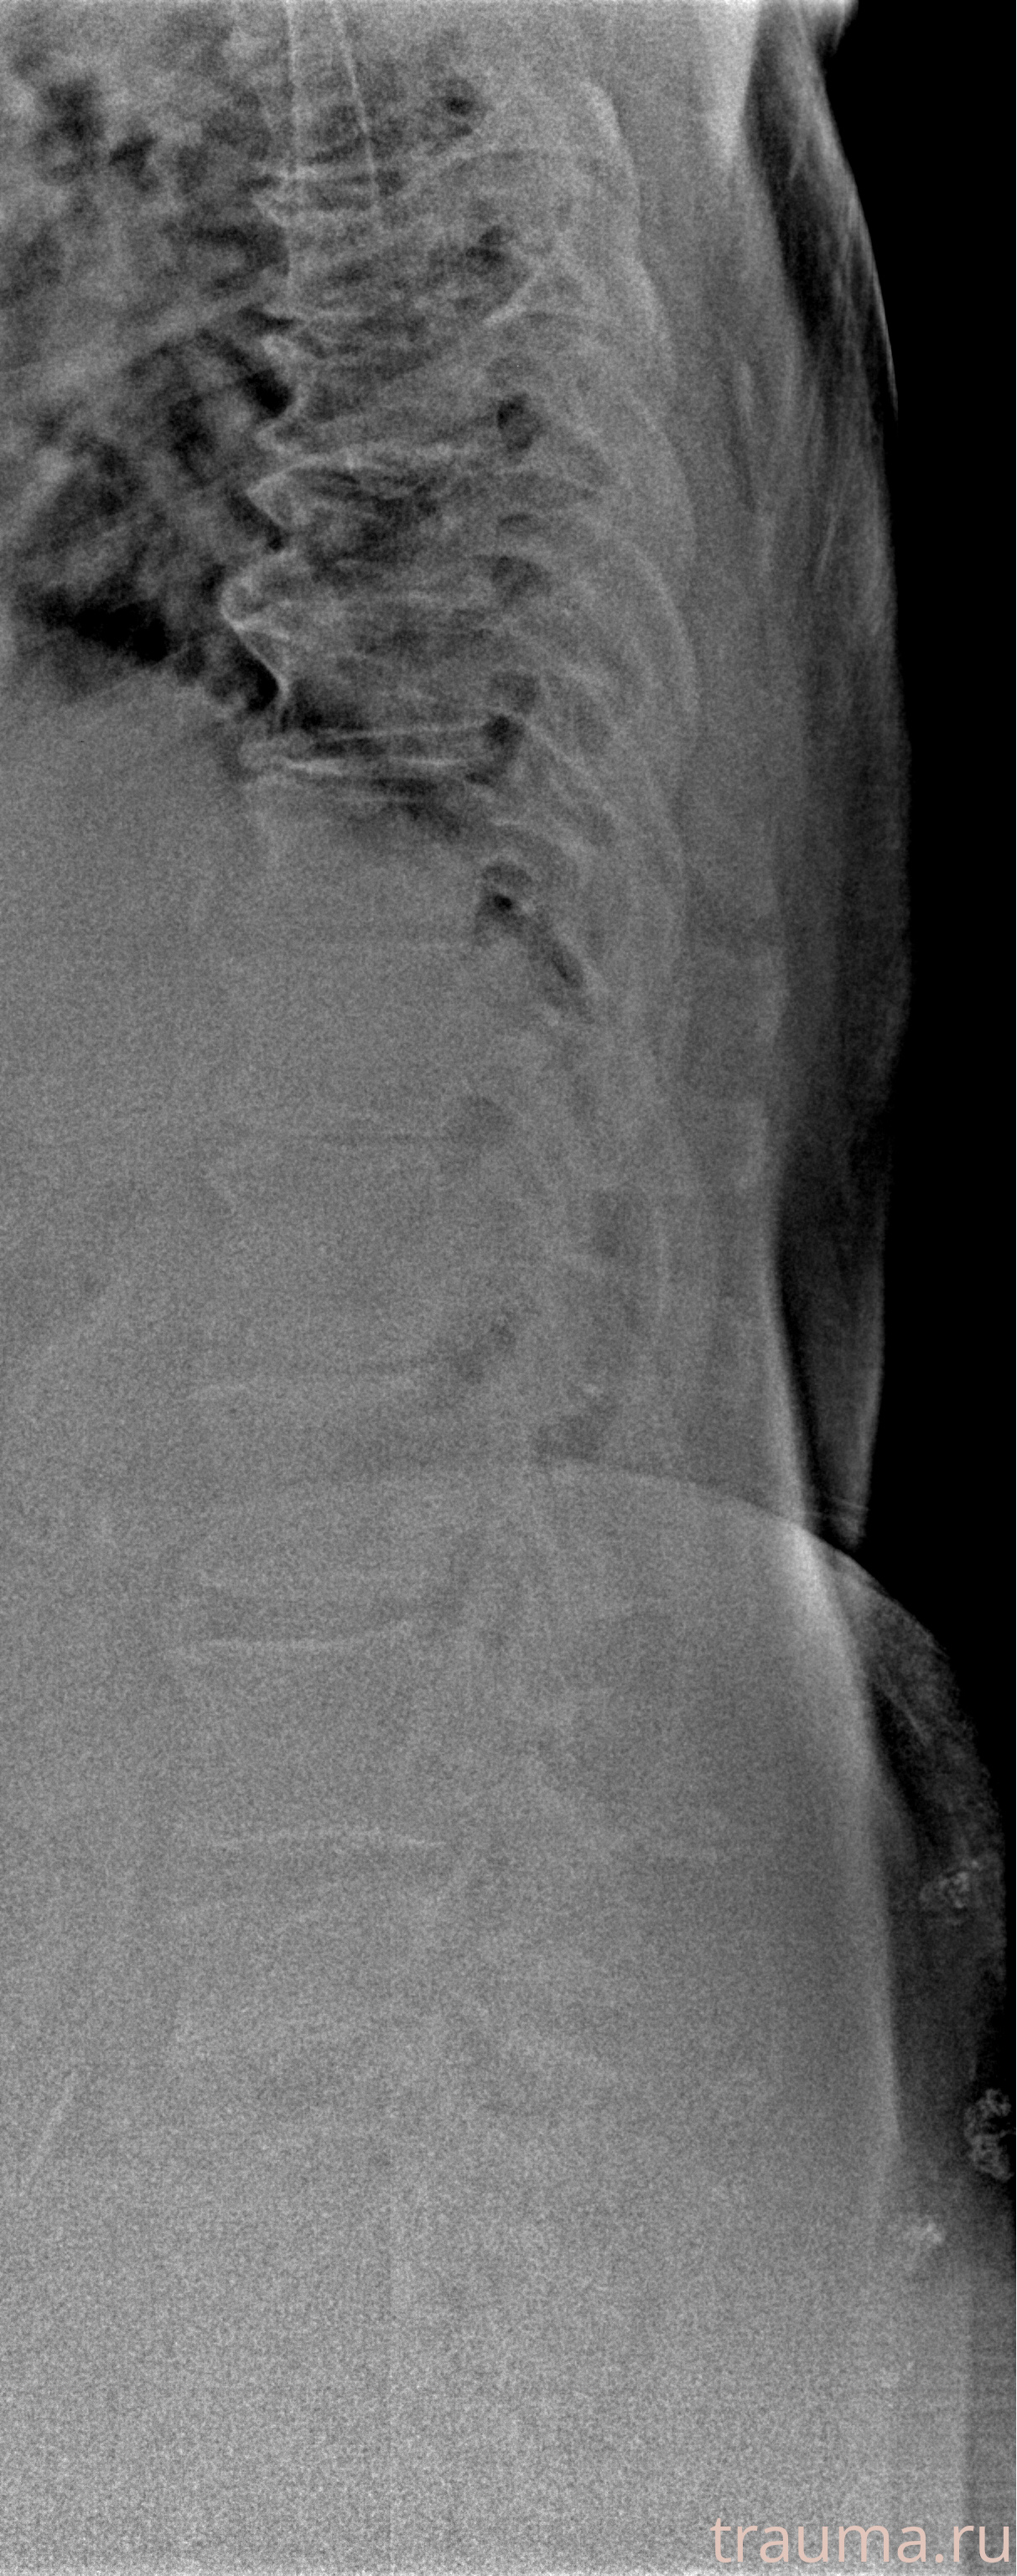

Рентгенограммы

Рентген на дому: по вашему адресу приезжает врач-рентгенолог, травматолог-ортопед с мобильным рентгеновским аппаратом, проводит диагностику травмы или заболевания, делает необходимые рентгенограммы, дает рекомендации по дальнейшему лечению. Получить качественные снимки в домашних условиях возможно благодаря уникальной методике, разработанной МосРентген Центром для института  Склифосовского